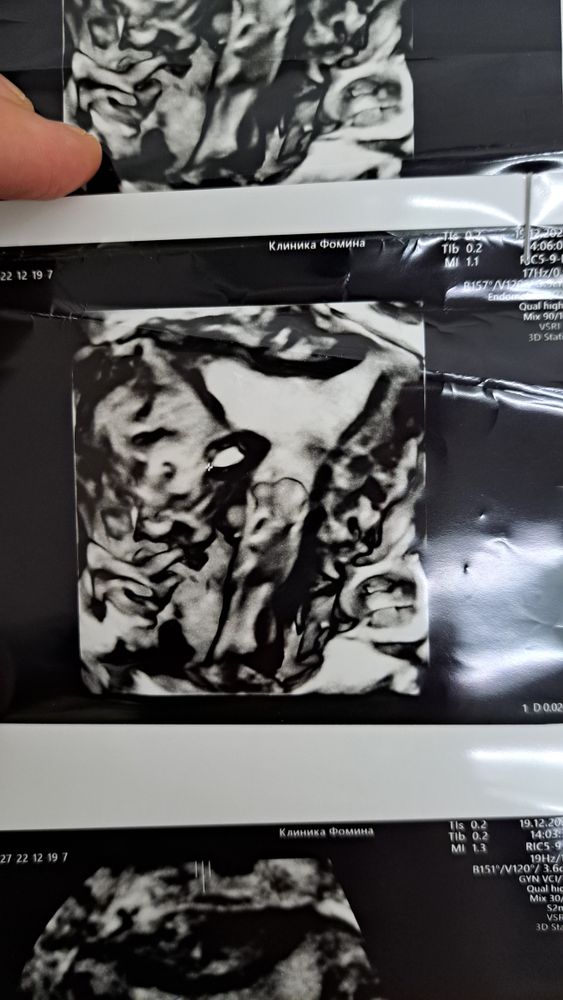

Арина, вот кстати фото 3д узи. Изображение Изображение Изображение Изображение Изображение в этом треугольнике серенькое - это эндометрий. и он однородный типа. справа кальценат. а вот блиде к шейке какая то фигня